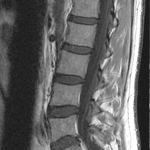

この場合はどうでしょうか?一番下とその上の椎間板が少し形が変わっていますが、脊髄の圧迫はありません。

この2枚のMRI画像のように全く違う状態なのに症状はほとんど変わらないということも良くあるのですが、整形外科ではもうどっちがどう違うのか全く分からなくなっていて病院によっても言うことが全然違うなんてことも少なくありません。